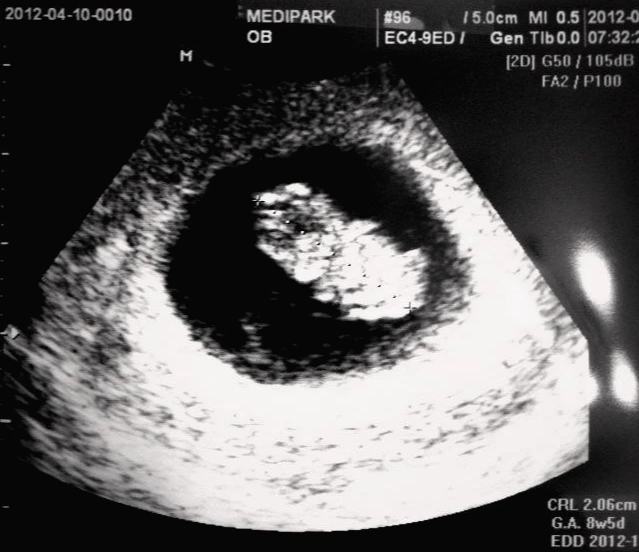

"임신입니다. 9주 네요. 어떻게 여태 모르셨습니까?!" 의사가 황당한 표정으로 말한다.

초음파를 보는데 2.06cm라는 아이는 신기했다. 그리고 간호사의 안내에 따라 산모수첩과 육아지원금 카드 신청이 진행되었고 나는 그렇게 엄마가 되었다. 그렇게 캐나다 여행은 물 건너 갔다.